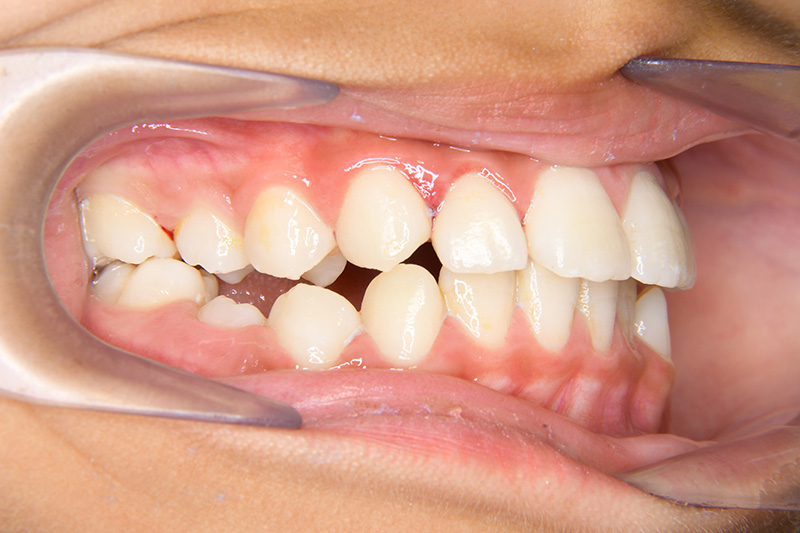

| 口腔内所見 | over jet 2.5mm、over bite 2.0mm、右側大臼歯関係はEnd on class Ⅱ、上顎左側Eは早期喪失により左側大臼歯関係はFull classⅡ、右側Eは6の異所萌出により歯根吸収が進行したため一般歯科医院にて抜去済みであった。 |

| 批評・予后 | 早期に6の遠心移動を行いナンスのホールディングアーチにて保隙をした結果、5は良好な状態で萌出できたように思う。 今後は永久歯列完成まで経過観察を行っていく予定である。 |